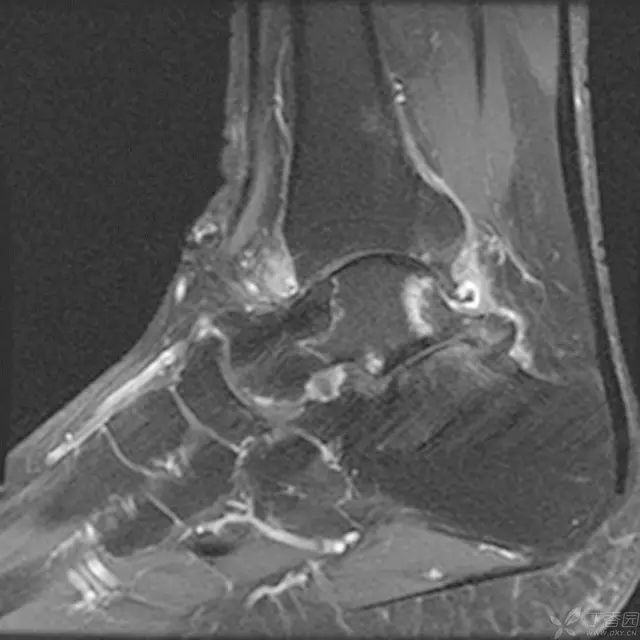

术后 2 周 MRI,没有急性炎症反应

6 个月,有轻度信号改变,表明存在一定程度的生理活动,无骨坏死征象

术后 2 年 MRI,弥漫性信号改变,符合早期骨坏死,但无塌陷

5 年 MRI,弥漫性信号局限在距骨体中心部位,头颈部逐渐出现血运重建,无塌陷